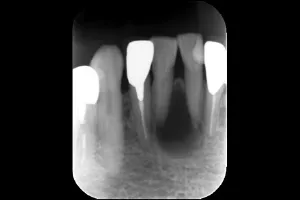

Case.01

治療前

治療中

治療後

治療前後の比較

| 治療名 | 根管治療 |

| 患者様情報 | 76歳 女性 |

| 担当医 | 岸田 義弘 先生 |

| 費用 | 1根管33,000円~ |

| 主訴 | 下の前歯の歯茎が腫れて痛い |

| 治療期間 | 約2ヶ月 (月1〜2回) |

| 治療内容 | 1.歯髄が生きているかどうかの確認 2.根管治療 3.修復治療 4.経過観察 治療の結果腫れもなくなり、歯の移動も戻りました。 |

| 治療のリスク | 術後2~3日後に痛みが出ることあります。術後1年程経過を追って、治癒傾向があれば経過観察、病変の拡大を認めるならば外科的対応になる可能性があります。 |